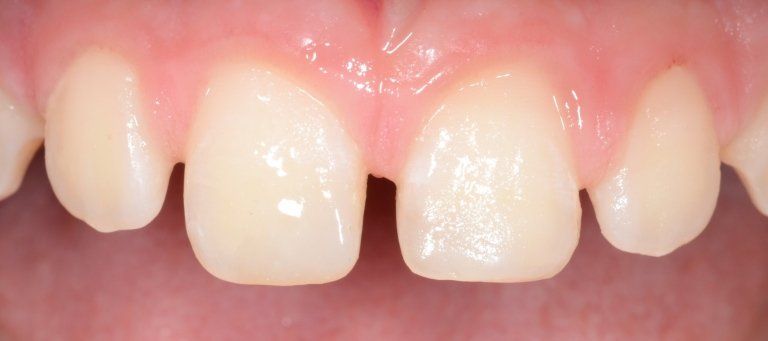

Frequenti, in età pediatrica, sono i traumi (sportivi e non). Come conseguenza i denti anteriori superiori (ovvero gli incisivi) sono i più esposti all’evento che può esitare in una frattura della corona con o senza il coinvolgimento della polpa, nella necrosi del dente (che può avvenire, più facilmente, senza alcuna frattura della corona dentale), oppure in quel panel di complicanze che vanno dalla lussazione ai traumi intrusivi o estrusivi, fino all’ avulsione, cioè la fuoriuscita completa del dente dall’alveolo.

I denti da latte traumatizzati più spesso vanno incontro a necrosi con conseguente cambiamento di colore, divenendo grigiastri, segno della morte delle cellule della polpa dentaria. In altre occasioni, il dente può fratturarsi in maniera più o meno ampia: se il frammento viene ritrovato, potrà essere re-incollato in maniera invisibile, oppure verrà ricostruito con i materiali compositi.